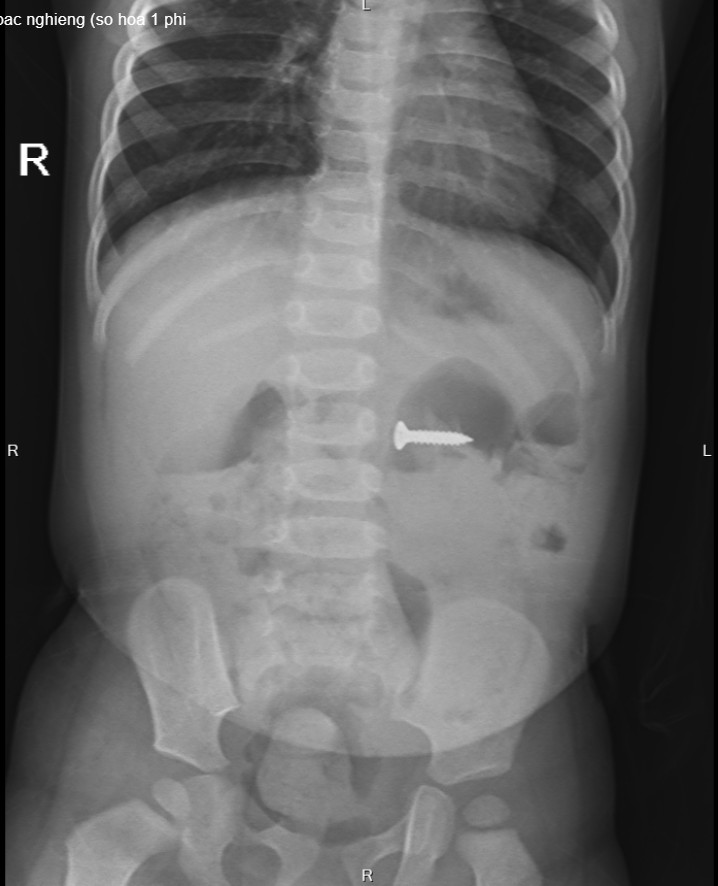

Tại Bệnh viện Sản nhi tỉnh Phú Thọ, các bác phát hiện dị vật đinh vít sắc nhọn kích thước 2 cm trong dạ dày. Với tính chất sắc nhọn, nếu không loại bỏ kịp thời, đinh vít có thể gây tổn thương đâm thủng thành ruột, dạ dày, thậm chí có thể gây tổn thương nhiều vị trí mà chiếc đinh đi qua.

Hình ảnh chụp XQ phát hiện đinh vít nhọn nằm trong dạ dày của trẻ.